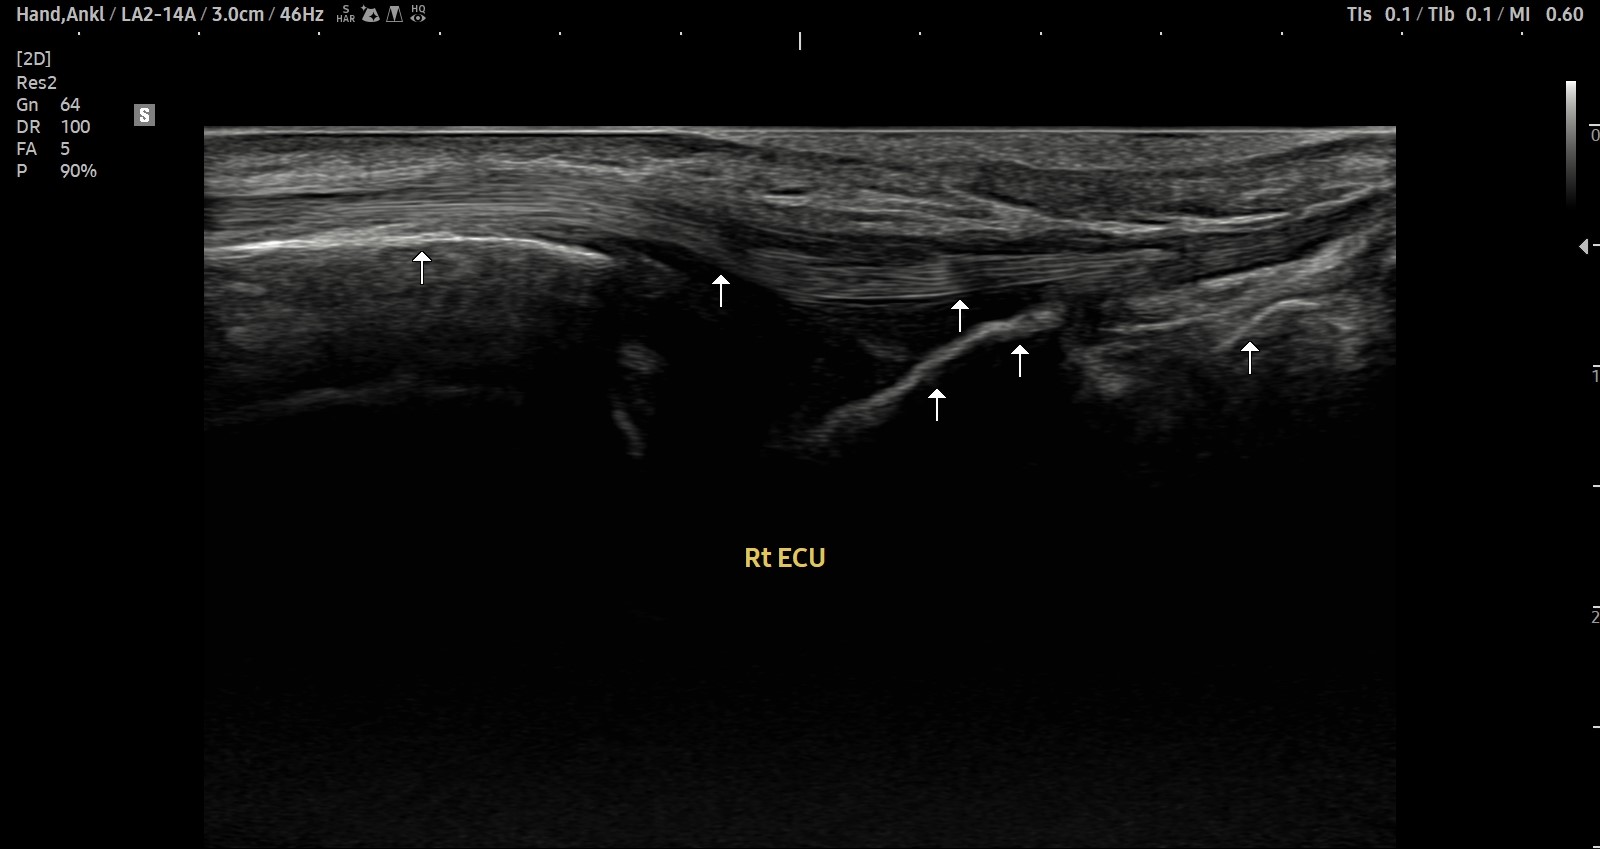

- 치료기간 : 25 .5 30 . ~ 25 . 6 .27

- 치료횟수 : 5 회(dna 1cycle)

양 손목 신근지대 건초염 & 건염

치료 전

치료 후